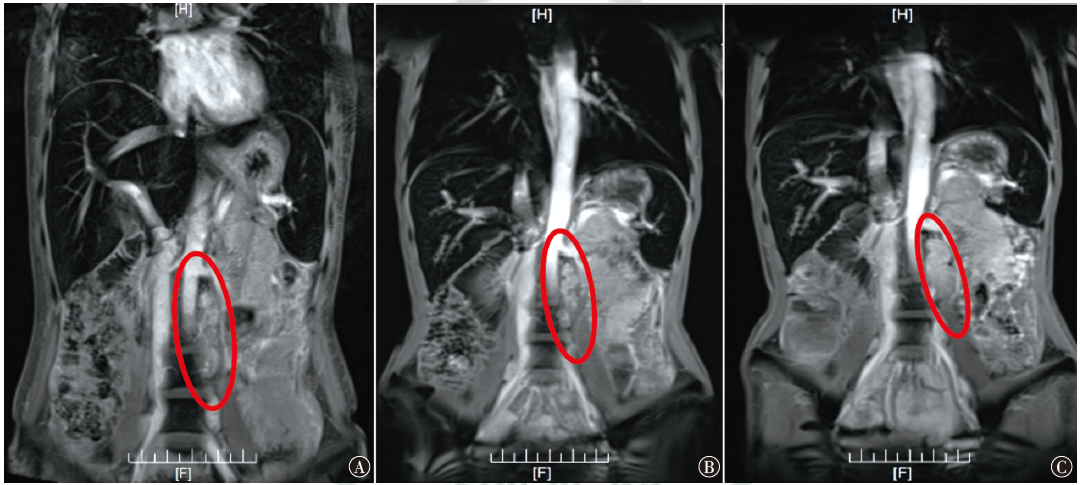

恶性腹膜间皮瘤是原发于腹膜间皮细胞的一种罕见恶性肿瘤,本例恶性腹膜间皮瘤晚期患者,通过特瑞普利单抗联合安罗替尼治疗后,CA125降至正常,病灶评估达到稳定,患者临床获益明显。该治疗方案对提高患者生命质量、稳定病灶起到了一定的作用。